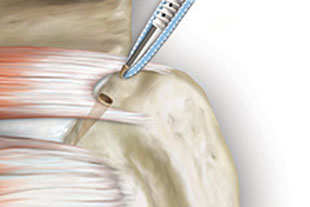

Versenken des Fadenankers unter der Knochenoberfläche

Einbringen des am Anker befestigten Fadens in die Sehne